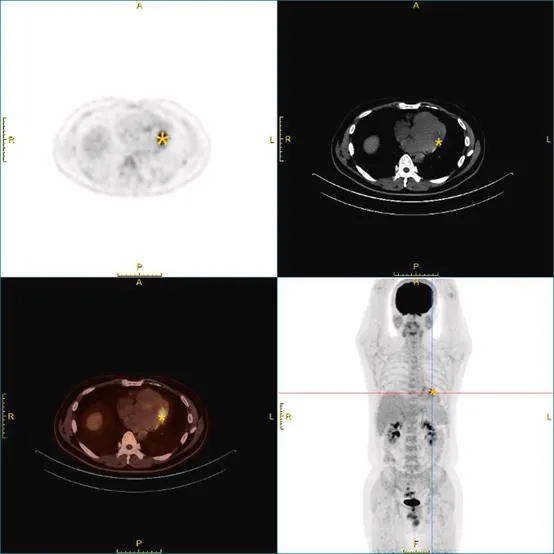

超声造影显示团块内部灌注程度较邻近心肌组织轻度减低。CT平扫可见一低密度病灶(CT值:54 HU),形态欠规则,部分与腱索结构相融合(图1C、1D)。心脏磁共振成像于左心室游离壁旁见一大小约33×19×20mm的团块,T2加权压脂序列上呈均匀高信号(图1E)。延迟增强扫描显示病灶早期未见强化,而于延迟期出现显著的“云絮状”强化表现(图1F)。此外,FDG-PET/CT扫描提示病灶代谢活性中度增高,SUVmax为7.8,该表现与周围心肌的生理性摄取同时存在(图2)。依据影像判读标准,该SUVmax低于10.1的良性阈值。尽管部分多模态影像学特征曾提示恶性可能,但综合其CT低密度、CMR T2均匀高信号、延迟期云絮状强化以及PET/CT所示中度代谢活性等表现,整体影像特征更加符合良性病变。

图2 ¹⁸F-FDG PET/CT影像表现

PET/CT融合图像显示病灶区域FDG摄取中度增高(SUVmax=7.8),周围心肌可见生理性摄取。

多模态影像学在本例诊断中发挥了关键作用:CT显示低密度病灶(54 HU);心脏磁共振(CMR)见均匀T2高信号,提示黏液样基质含水量高;延迟期“云絮状”强化(由钆对比剂在富含黏多糖的间质内聚集所致)是提示良性的关键指标,尽管存在明显的心肌浸润;PET/CT显示中度FDG摄取(SUVmax=7.8),低于>10的恶性阈值。